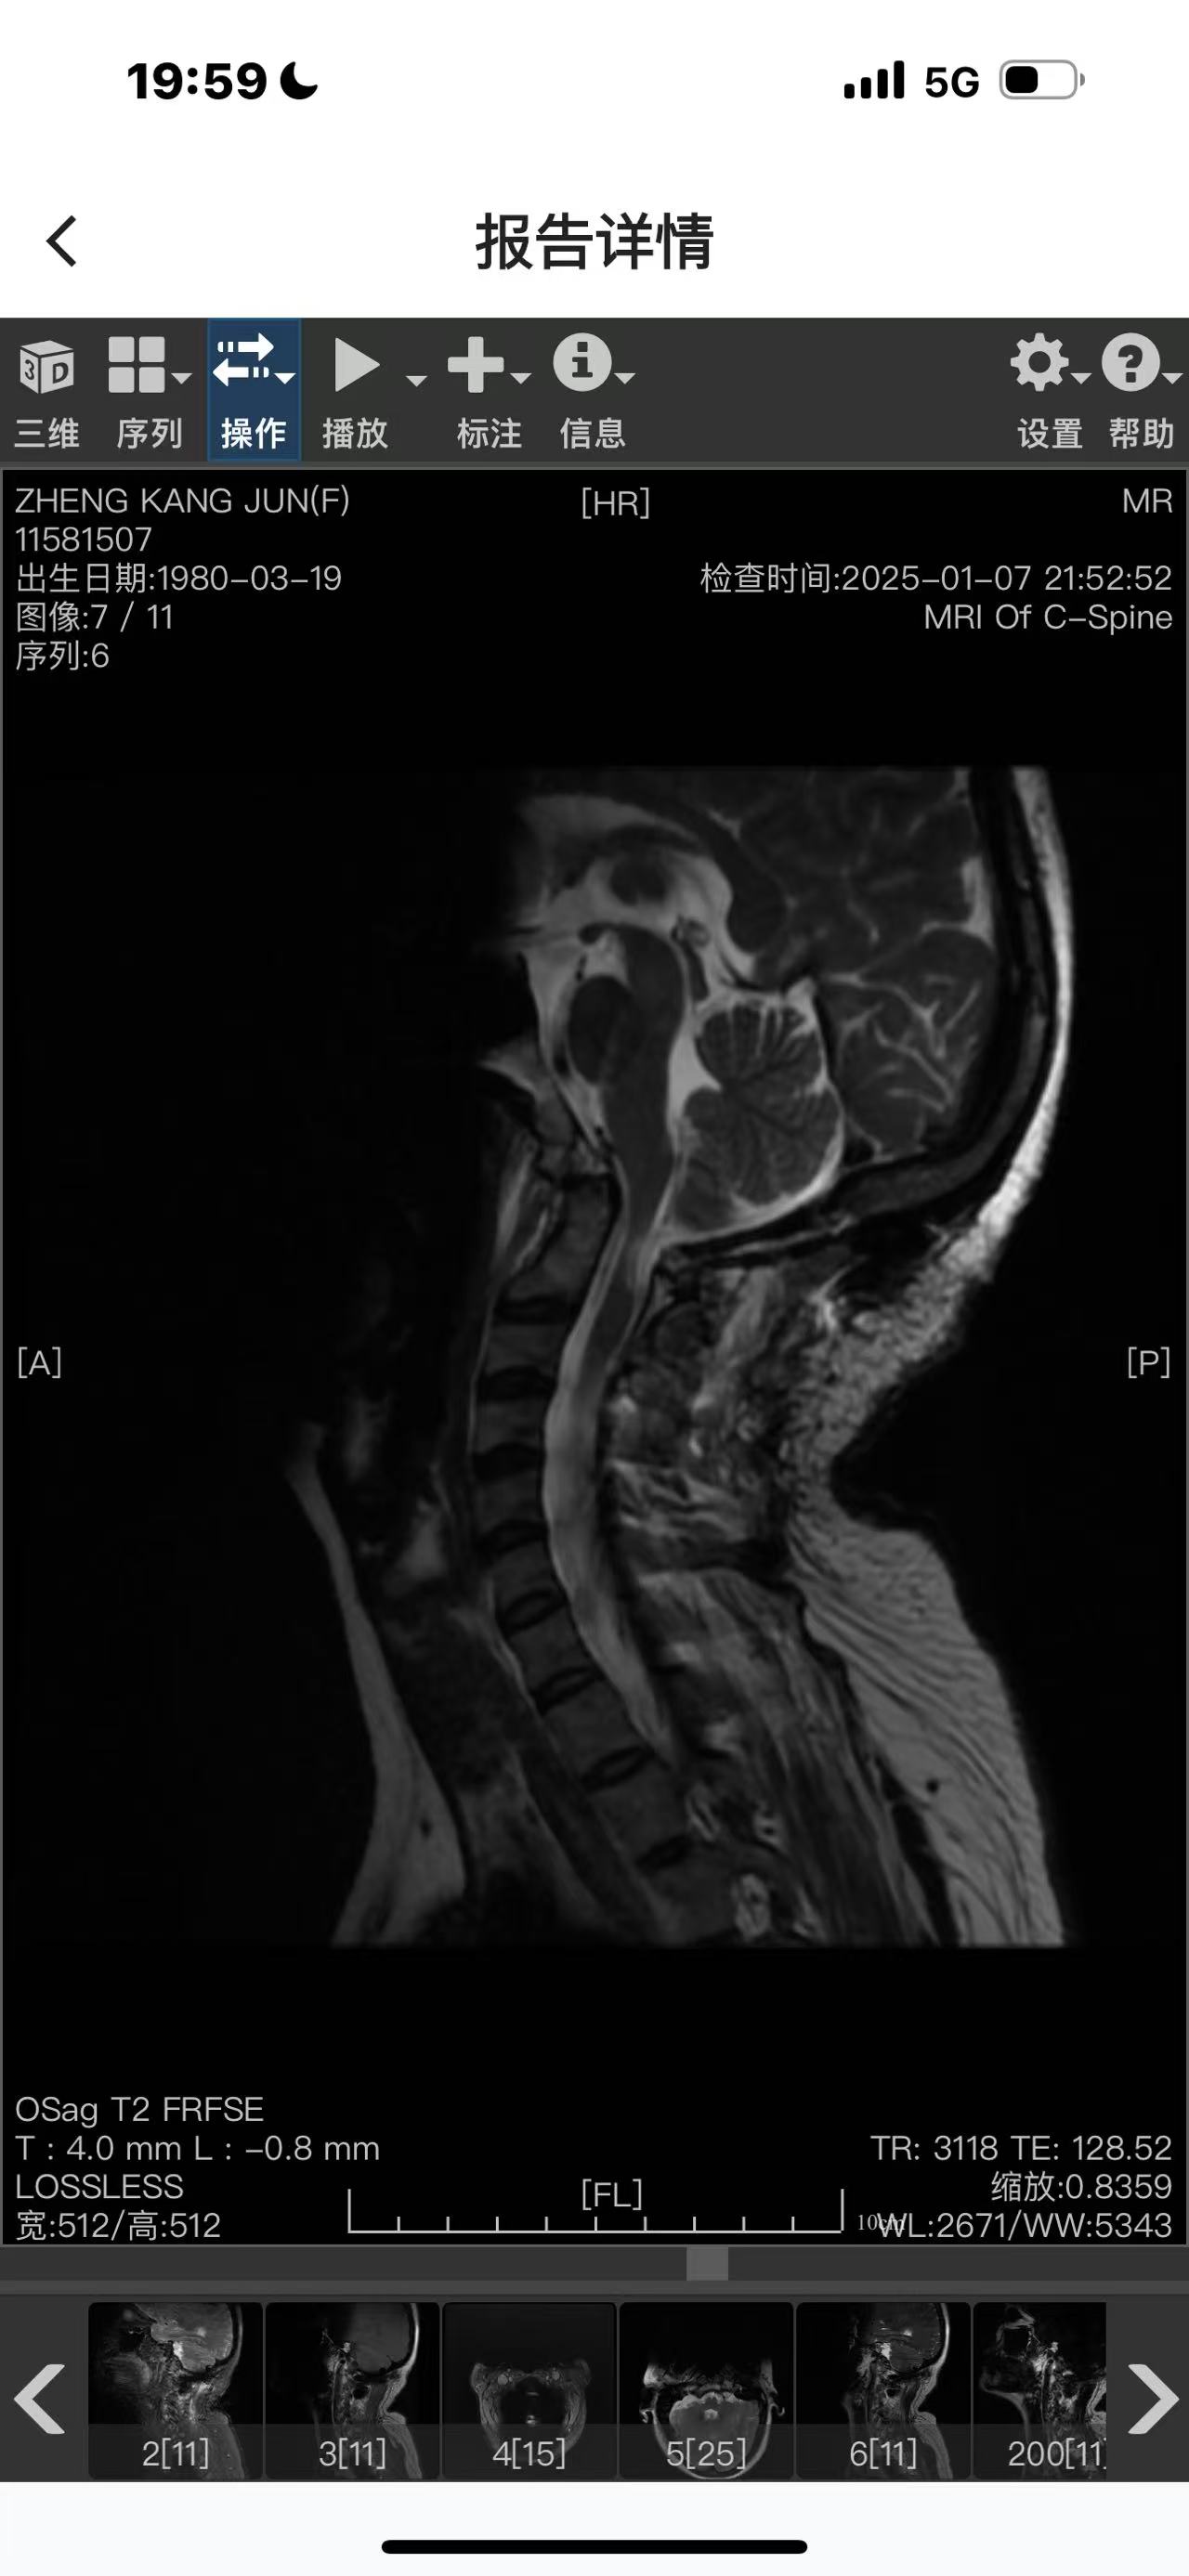

• 诊断:寰枢椎脱位

二次手术#

• 日期:2024.12.30

• 医院:人民医院

• 主刀:王超

• 术后影像: